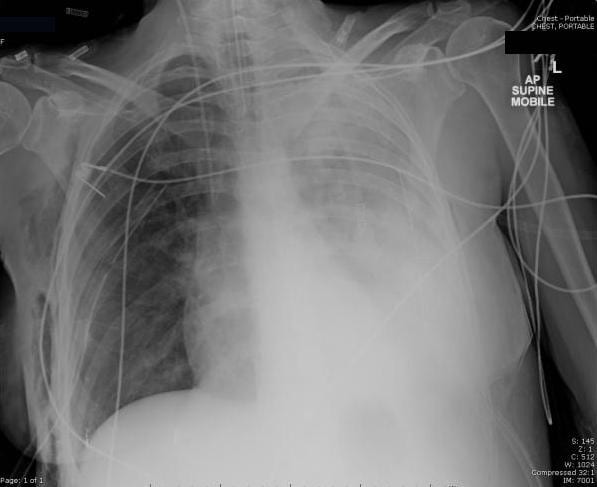

What's your diagnosis from this chest X-ray? Our friends at Medmastery made their Chest X-ray Essentials workshop for free until May 19th! Check it out here -> medmastery.com/workshops/ches… #FOAMed #radiology #chestxray #MedEd #MedTwitter

What abnormalities do you see? By the way: Chest X-ray Essentials course over at Medmastery is still free until May 19th -> medmastery.com/workshops/ches… #FOAMed #MedEd #MedTwitter #Radiology #ChestXray